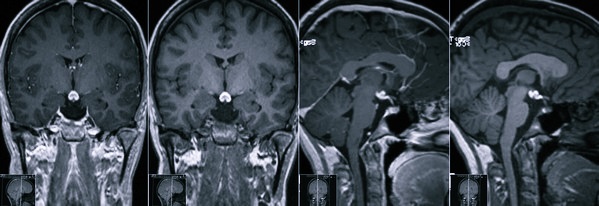

Аденома гипофиза — это доброкачественная опухоль, которая развивается из клеток гипофиза, расположенного в основании мозга. Врачи отмечают, что такие опухоли могут вызывать разнообразные симптомы в зависимости от их размера и типа. Например, некоторые аденомы выделяют гормоны, что может приводить к эндокринным нарушениям, таким как акромегалия или синдром Кушинга. Врачи подчеркивают, что ранняя диагностика имеет ключевое значение для успешного лечения. Методы визуализации, такие как МРТ, помогают выявить опухоль, а лечение может включать медикаментозную терапию, хирургическое вмешательство или радиотерапию. Важно, чтобы пациенты были осведомлены о возможных симптомах и своевременно обращались за медицинской помощью.

- Проведение магниторезонансной терапии и КТ (компьютерная томография).